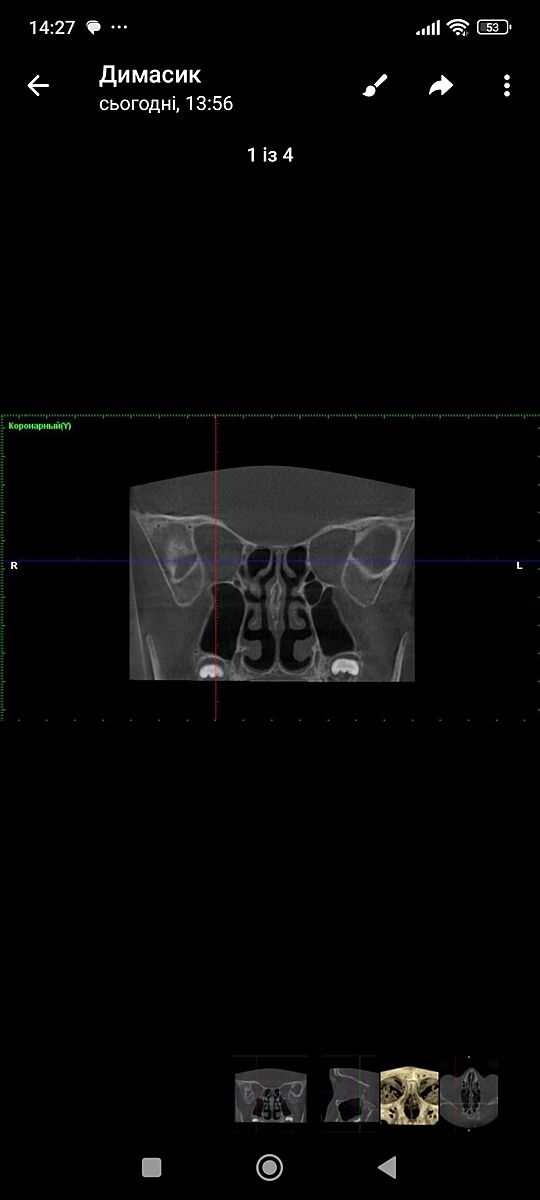

КТ ППН хто розуміється

Що ви тут бачите?

Синусита и ринита нет

Но на скане нет лобных пазух